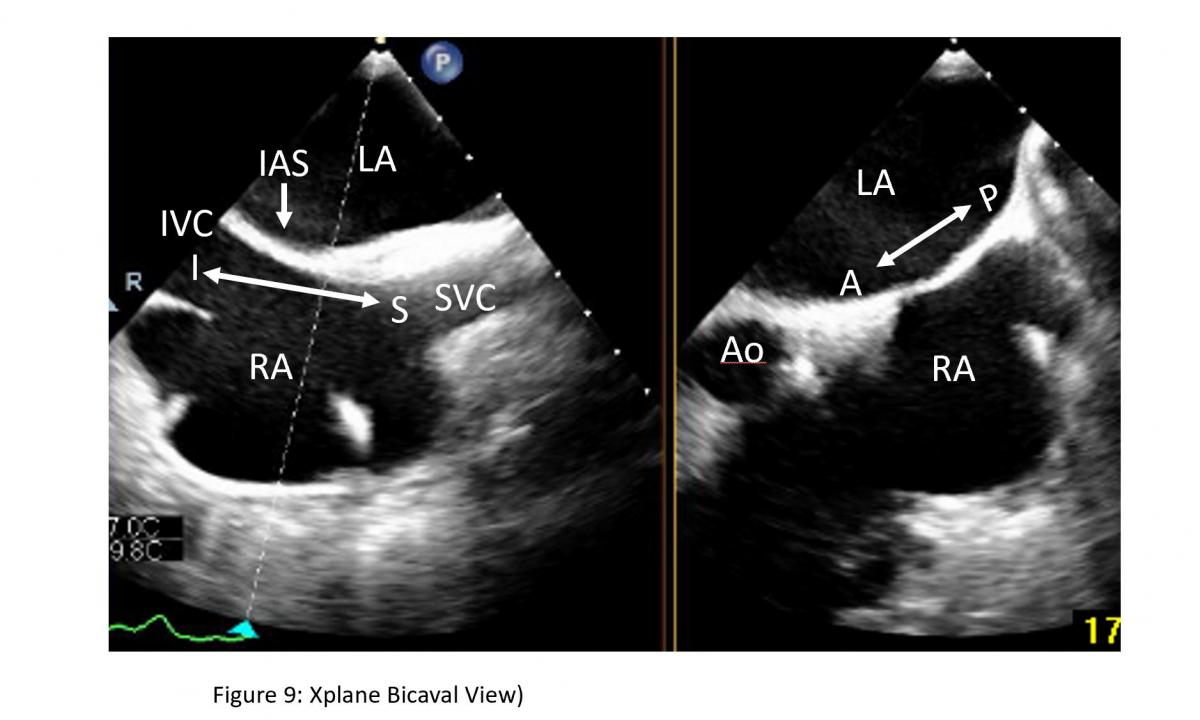

Figure 9: Bicaval view and short-axis view of interatrial septum on a Xplane TEE image: Bicaval view for superior as noted by superior vena cava (SVC) ) and inferior noted by inferior vena cava (IVC) direction of interatrial septum (IAS) can be obtained from TEE probe section rotation at 100-120 degree with medial rotation of the probe at mid esophageal level. LA: left atrium, RA: right atrium, Ao: aorta

Location of the transseptal puncture is important. The optimal puncture site is in the membranous part of interatrial septum (IAS) superiorly towards the mid septum and posteriorly of the interatrial septum.  The newer clips NTR and XTR requires more mid superior-inferior and posterior septal puncture. Three TEE planes are used to determine the correct site:

• a short-axis view at the base for anterior-posterior orientation; aortic valve in short axis as an anterior landmark

• a bi-caval view for superior (cranial)- caudal (inferior) orientation/110-degree view

• a four-chamber view to direct the height above the mitral valve

The position of the BRK transseptal needle (St. Jude Medical, Inc, St Paul, Minnesota, USA) can be seen by a tent-like indentation of the interatrial septum (‘tenting’) (Figure 11) Thereby, the tip of the ‘tent’ points towards the left atrium. With a satisfactory posterior and superior location, the height above the valve is assessed in a four-chamber view (Figure 12).